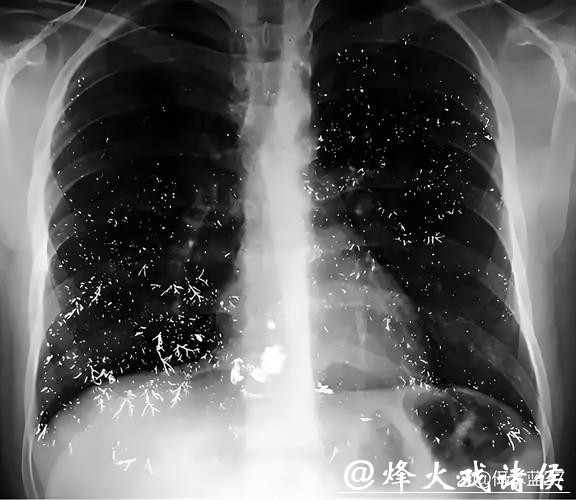

医生在详细询问病史、结合胸部CT影像及相关免疫学检查后,排除感染性肺炎、哮喘等常见病因,最终考虑为典型的羽绒相关性过敏性肺泡炎。在明确病因后,医生一方面给与激素等抗炎、抗过敏治疗,另一方面严肃提醒他立刻停止接触破损羽绒服,避免再吸入羽绒碎屑。短时间规范治疗后,男子的呼吸症状有所好转,但医生仍警告他:如果继续忽视,未来可能面临肺功能不可逆损害。